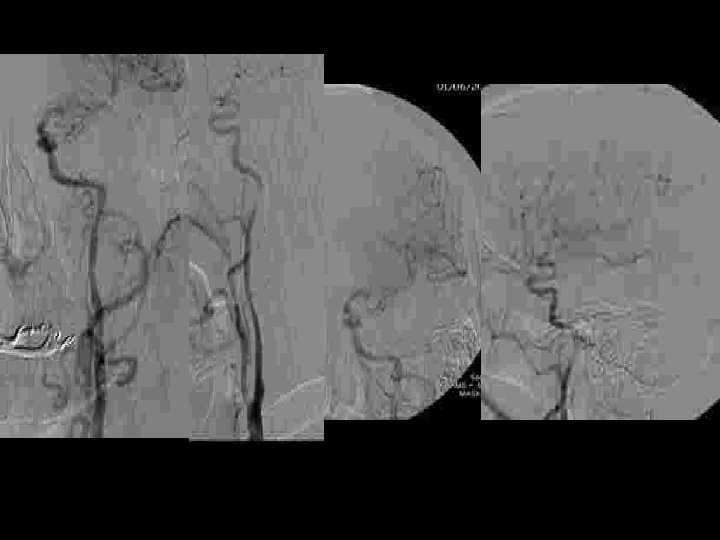

Carotide cervicale

THROMBO ASPIRATION

Après THROMBO ASPIRATION

stent + protection device + angioplastie

Destruction mécanique du caillot • Thrombo-aspiration • Fragmentation – Injections pulsées – Guides – Ballons: angioplasties – Stents – Ultrasons • Retrait